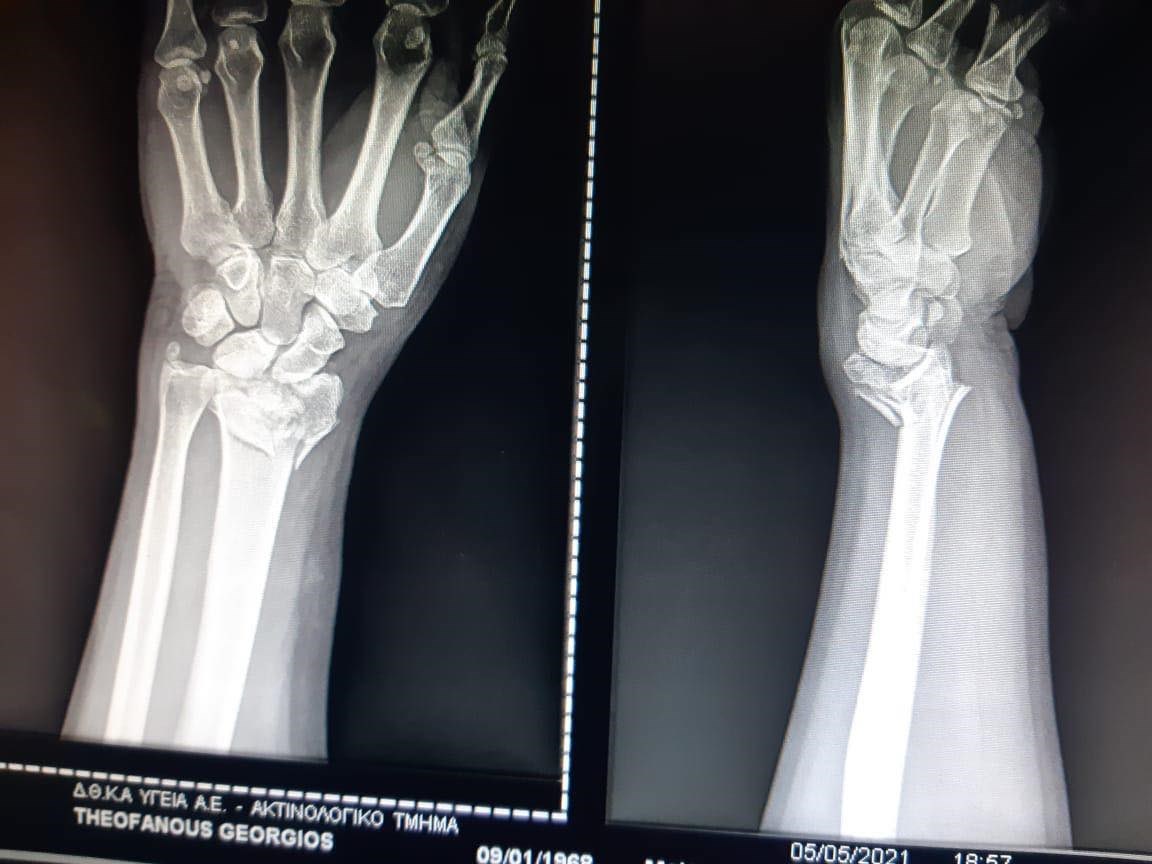

Γιώργος Θεοφάνους: Το κάταγμα στο χέρι και οι πρώτες δηλώσεις – ΒΙΝΤΕΟ

Ο Γιώργος Θεοφάνους νοσηλεύεται στο νοσοκομείο έπειτα από ατύχημα που είχε. Ο γνωστός συνθέτης τραυματίστηκε στο αριστερό του χέρι και υποβλήθηκε σε χειρουργείο. Με δήλωσή του στην εκπομπή του ΑΝΤ1 “Το Πρωινό”, αποκάλυψε ότι η πρώτη επέμβαση πήγε καλά αλλά θα χρειαστεί και δεύτερη σε περίπου έναν μήνα. “Το πρώτο χειρουργείο πήγε μια χαρά, σε κανένα μήνα το δεύτερο. Όλα δείχνουν καλά. Και όπως μου έγραψε με χιούμορ η Αλεξίου: “Τώρα θα παίζεις με το αριστερό, όπως παίζω εγώ με το ένα δάχτυλο” ανέφερε χαρακτηριστικά.

Ο συνθέτης μάλλον έπεσε, αλλά δεν έχουν γίνει γνωστές περισσότερες λεπτομέρειες για το ατύχημα. Όπως είπε ο Γιώργος Λιάγκας, ο τραυματισμός είναι σοβαρός καθώς υπέστη κάταγμα και η αποθεραπεία θα διαρκέσει τουλάχιστον δύο μήνες.